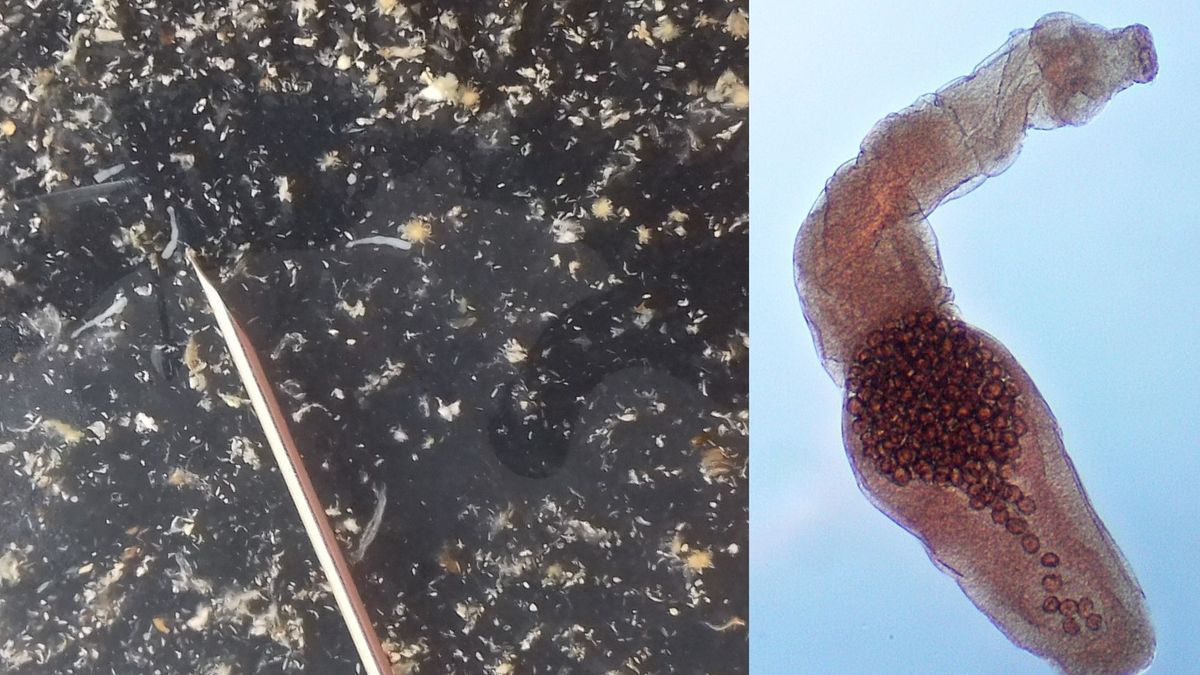

Magyarországon is mind gyakrabban fordul elő egy állatról emberre terjedő, galandféreg okozta betegség, az echinococcosis – hívja fel a figyelmet a Semmelweis Egyetem az MTI-hez szerdán eljuttatott közleményében.

Magyarországon is mind gyakrabban fordul elő egy állatról emberre terjedő, galandféreg okozta betegség, az echinococcosis - hívja fel a figyelmet a Semmelweis Egyetem az MTI-hez szerdán eljuttatott közleményében. A Sürgős figyelmeztetés jött: Súlyos fertőzés terjed Magyarországon, egyre több a beteg bejegyzés először Most Hír -én jelent meg.

Dél-Magyarországon is egyre gyakrabban bukkan fel egy emberre is veszélyes galandféreg

A féreg fő célpontjai a rókák, sakálok, de sajnos előfordul, hogy emberben is kikötnek, és olyankor elég nagy a baj.